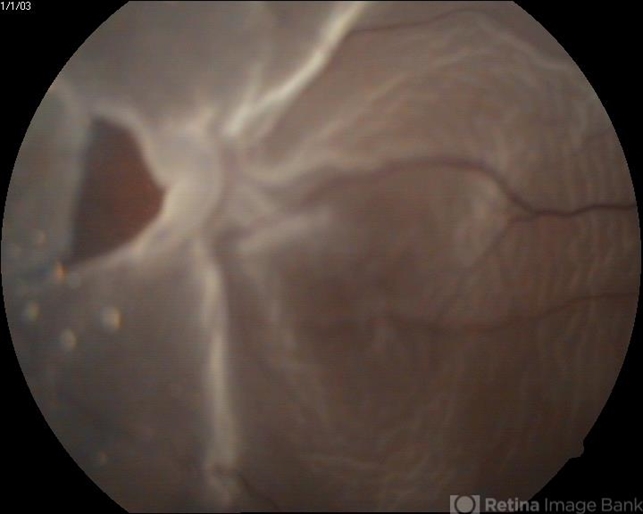

- A myopic male patient 23 years old presented to outdoor and found to have retinal detachment with horse shoe tear.